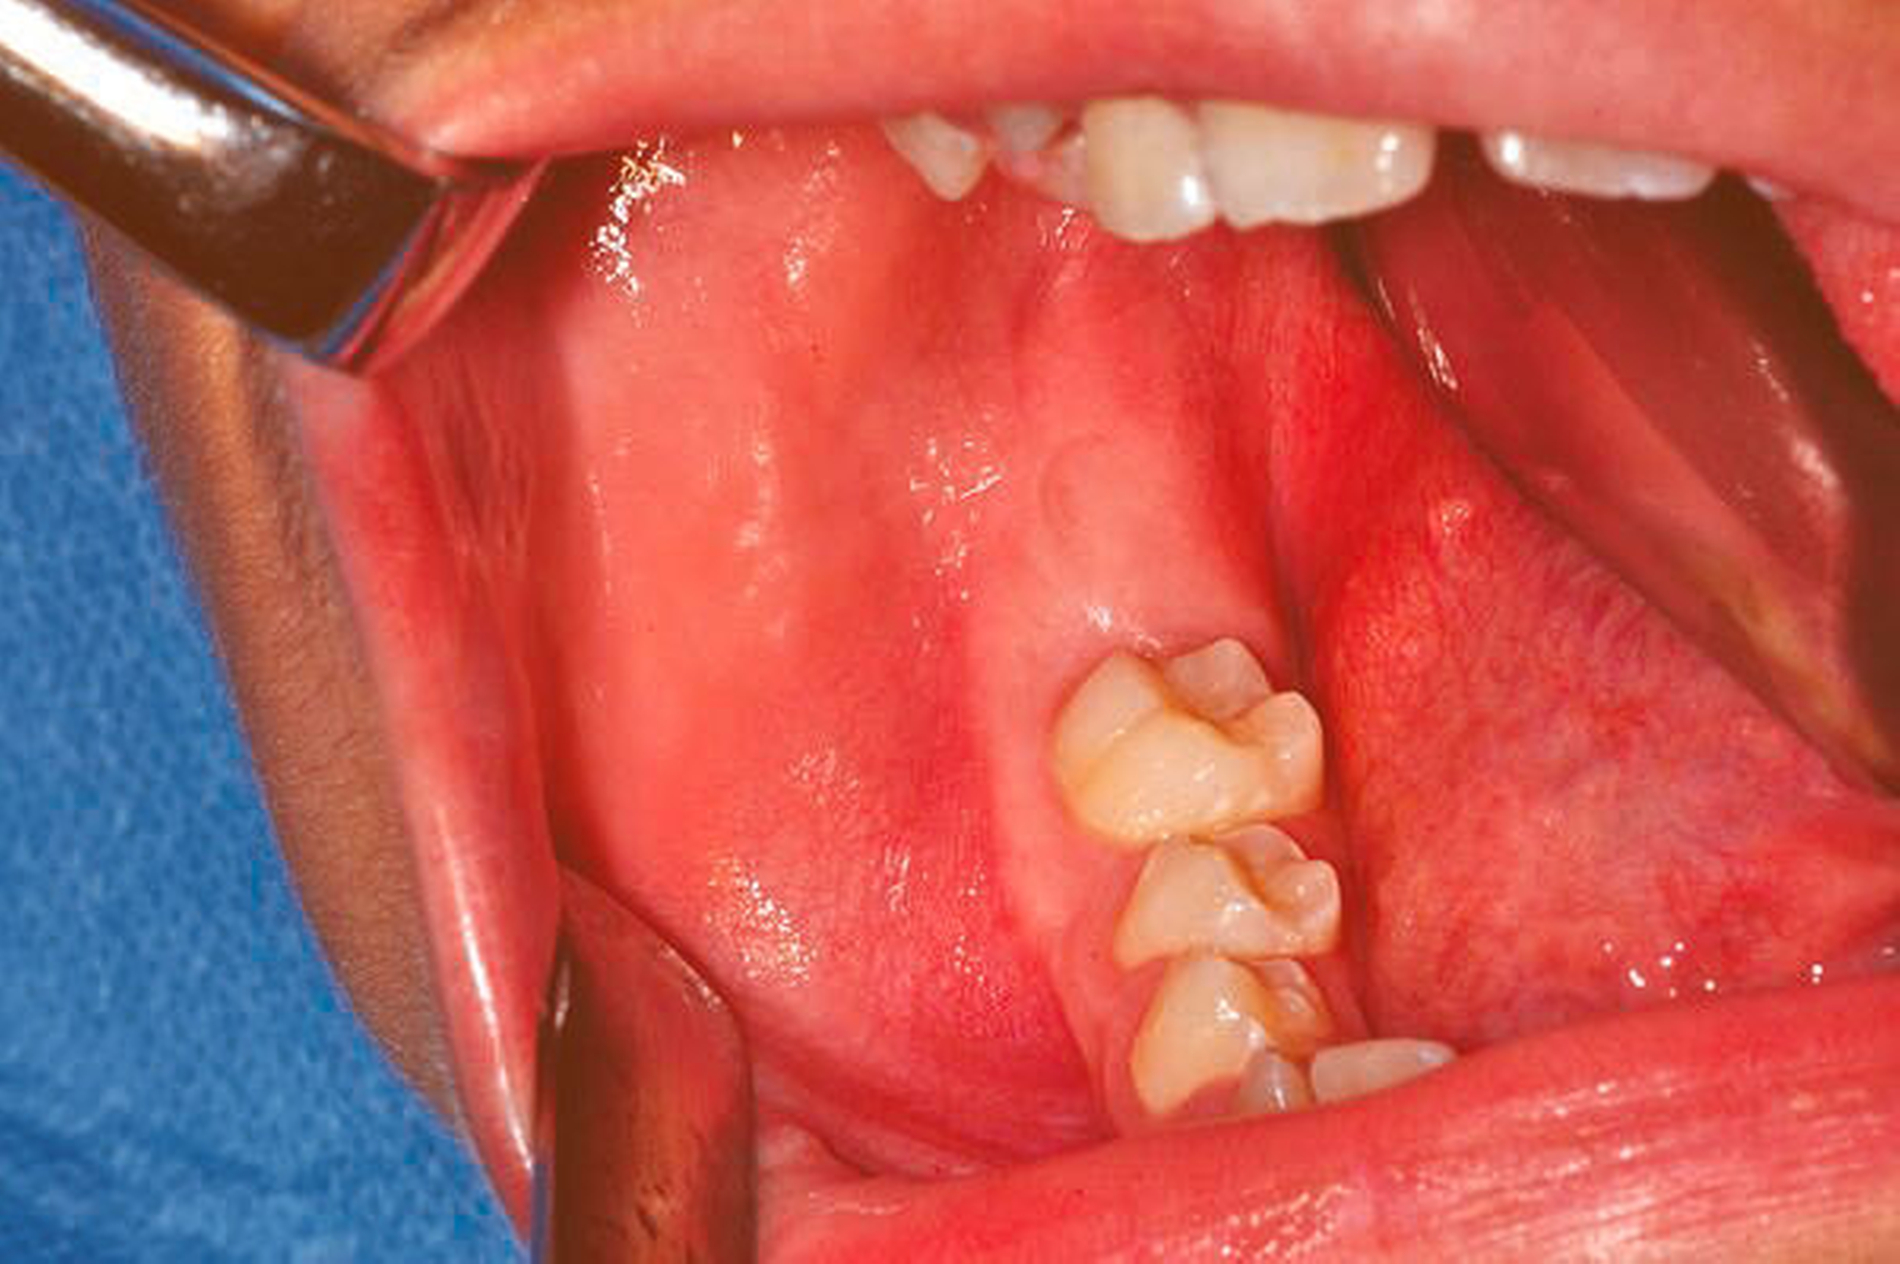

Klinisch zeigte sich eine nicht verschiebliche, harte und reizlose Schwellung mit erhaltender Vitalität distal des Zahns 46 und noch retinierten weiter posterior gelegenen Zähnen (Abbildung 1). Zur weiterführenden radiologischen Analyse wurde anschließend eine 3-D-Aufnahme (Digitale Volumentomografie, DVT) des Unterkiefers durchgeführt, auf der zu sehen war, dass sich die Zähne 47 und 48 in einer knöchern begrenzten, transluzenten, homogenen Höhle befanden (Abbildung 2).